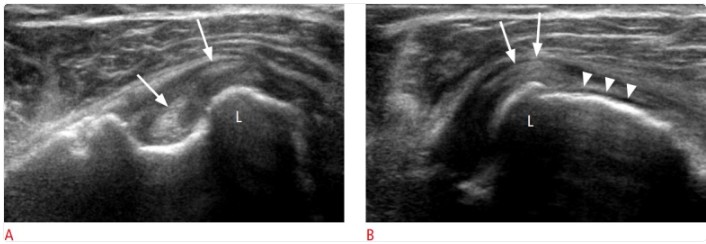

Ejemplo de exploración estática vs dinámica:

- A. En posición neutra, la porción larga del bíceps muestra una rotura longitudinal (flechas). Aunque el tendón sigue dentro de la corredera bicipital, su porción medial sobrepasa parcialmente la pared medial a nivel del tubérculo menor (L).

- B. Con la maniobra dinámica en rotación, esa porción medial lesionada se desplaza más hacia medial y se monta sobre el tubérculo menor (flechas). Además, se aprecia una rotura completa del subescapular en su inserción (cabezas de flecha), hallazgo que ayuda a explicar la pérdida de contención del bíceps.